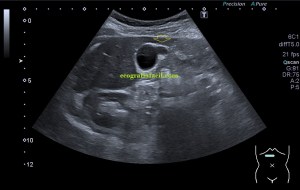

Durante la exploración de una eco de abdomen en el contexto de un paciente que acude por elevación de transaminasas observo una imagen heterogénea, irregular, con una pared marcadamente calcificada, bilobulada de gran tamaño que medí en dos partes ya que me pareció claramente que estaban diferenciadas.

Una de ellas, la primera, era mucho más hiperecogénica y más pequeña, su centro estaba mas calcificado, su sombra acústica posterior era mucho más acuciada y llamaba más la atención. Justo al lado, otra lesión de mayor tamaño, su calcificación era mucho más sutil y más periférica delimitando una LOE hipoecogénica de un tamaño muy importante, adyacente a la más pequeña, como he comentado previamente. Ambas sin señal Doppler.